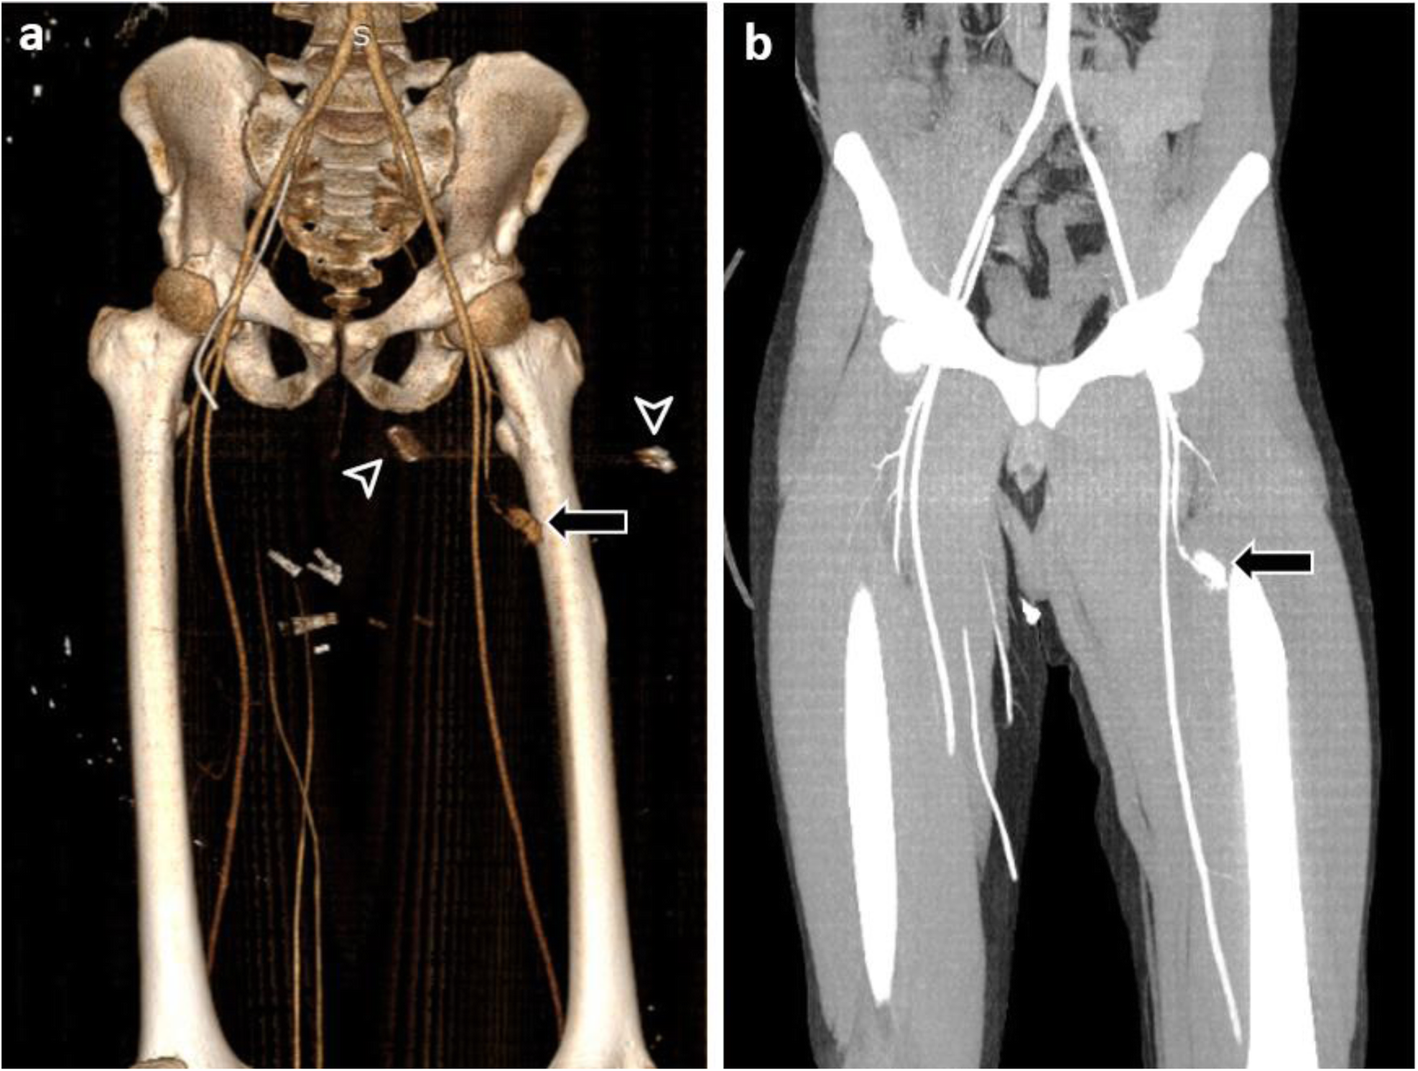

Fig. 4 | BMC Emergency Medicine